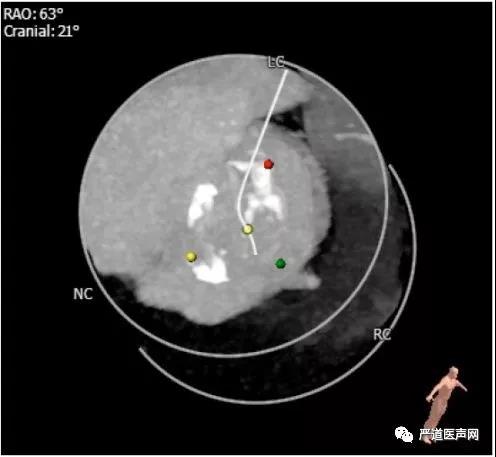

术前CT:

瓣环直径28.4 mm * 19.4 mm(平均径23.9mm)

周长76.8mm

面积444.7 mm2

乏氏窦直径26.5 mm * 33.4mm (平均径30.0 mm)

瓣膜中度钙化

横位心:成角57度